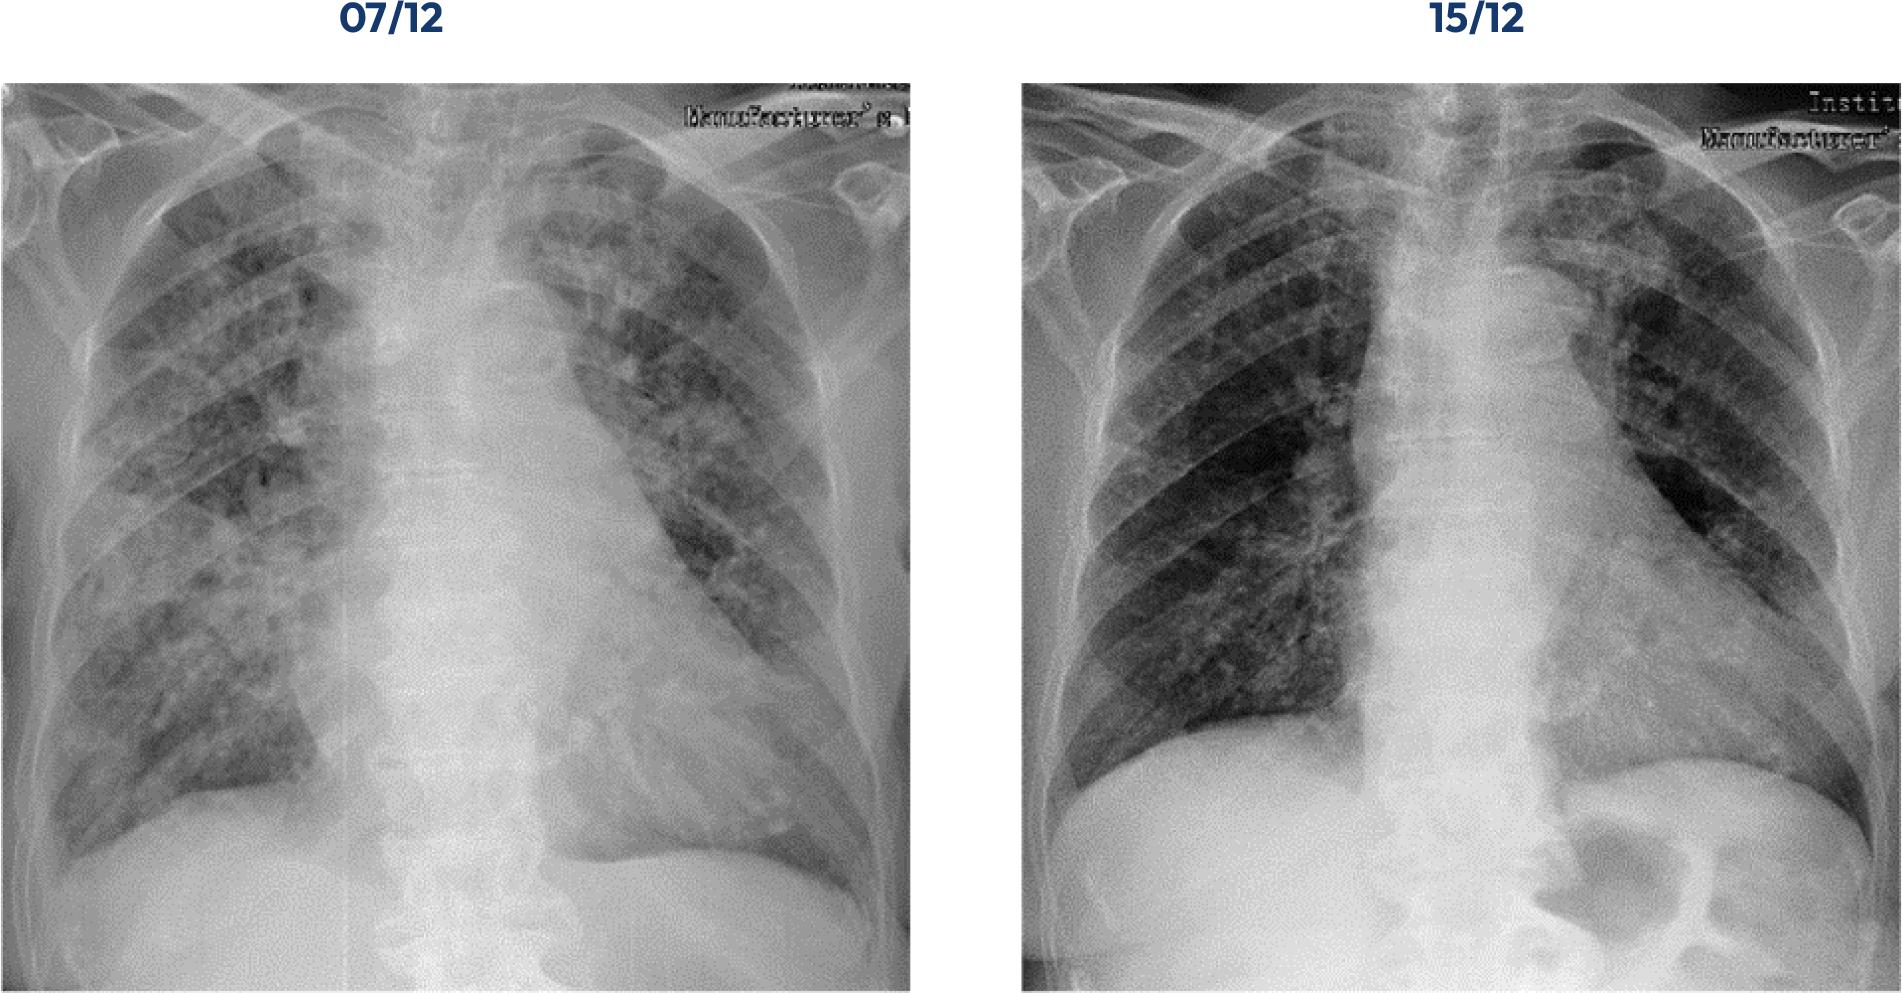

Neste tipo de doença, os exames complementares de diagnóstico são fundamentais para avaliar a patologia respiratória e a sua evolução. Na Figura 1, está presente a evolução imagiológica através de telerradiografia de tórax da Srª D. Maria.

A primeira imagem radiológica refere-se ao primeiro dia de internamento e, a segunda, ao dia da alta clínica. Percebe-se que a avaliação realizada através da auscultação pulmonar vai ao encontro do que este exame revela, existindo uma maior consolidação a nível do terço inferior direito e esquerdo. Além disso, está evidenciado um aumento da hipertransparência de ambos os campos pulmonares. Também a gasimetria arterial se traduz como importante, pois avalia as concentrações de oxigénio, ventilação e equilíbrio ácido-base(5). Na Tabela 8, encontram-se os resultados desta avaliação no primeiro e no último dia de internamento da Srª D. Maria.